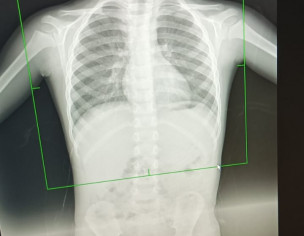

Asking for Other, Male, 4 years old, Okara

AOA Got this xray done for my son. He has cough and flu. Is it normal.

theek hai. flu ki wajah se dry cough ho gi , cough suppressant dein